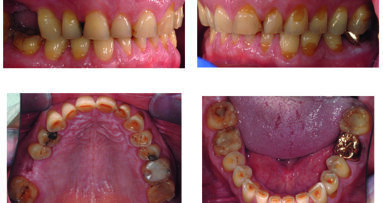

Nevis, mostro sacro perché? «Ma perché non credo vi sia nessuno al mondo che possa vantare dei follow up come i suoi ‒ osserva Cardaropoli ‒ visto che arrivano fin a 45 anni». Ricercatore e clinico al tempo stesso (cosa notoriamente piuttosto rara) puntualmente tradotto da Cardaropoli, Nevins ha infatti illustrato i suoi longevi “case reports” nella Sala Punt e Mes rimasta piena sino alla fine: casi trattati con l’ausilio delle tecniche di ingegneria tissutale (mediante fattori di crescita ricombinanti e proteine morfogenetiche dell'osso) che rappresentano il futura della rigenerazione ossea.